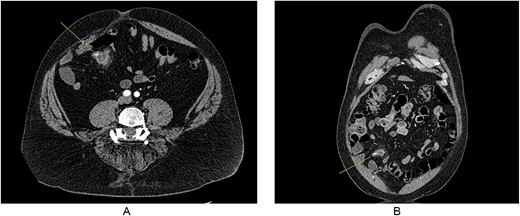

A 55-year-old male presented to the Emergency Department with right upper quadrant abdominal pain, nausea, and vomiting. A computed tomography (CT) scan (Fig. 1) revealed a linear foreign body that appeared to perforate the small bowel on the right side, accompanied by inflammation. No free air or fluid was observed. He did not recall ingesting anything containing bones. The decision was made to take the patient to the operating room for exploratory laparotomy, during which it was discovered that the patient had a partially perforated MD with inflammation and a foreign body inside (Figs 2 and 3). Inflammation and perforation were located at the distal end of the MD with a healthy base. Therefore, diverticulectomy was performed without any significant compromise or stricture of the ileum. The abdomen was then irrigated and closed, and the patient was transferred to the post-anesthesia care unit without any complications. The patient’s postoperative course was uncomplicated and he was discharged on postoperative Day 1.

CT imaging showing foreign body in MD, with some inflammation and fat stranding around it. (A) Coronal imaging and (B) cross-sectional.